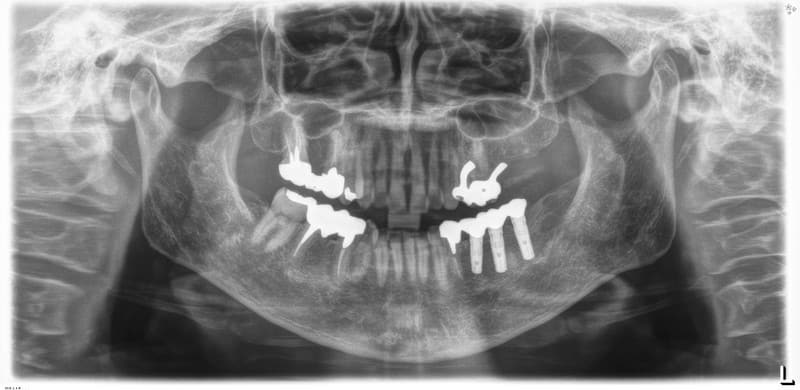

完全に歯がない場合

インプラント治療

インプラントを土台にして入れ歯を安定させ、動かず、しっかりした義歯にすることが出来ます。

また、あごの状態によってはインプラントによって一本ずつの歯を自然な状態で再建することも可能です。